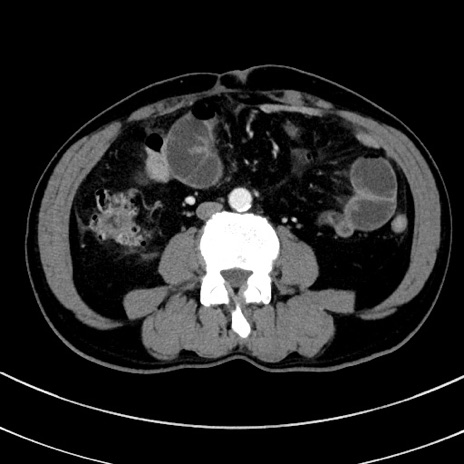

症例8(横断像)

【症例】 60歳代男性

【主訴】 黒色吐物

【現病歴】 4日前から嘔気自覚、2日前の朝食後にも嘔気あり、自分で手で嘔吐反射起こし嘔吐したところ血が混ざっていたため受診。

【既往歴】 5年前汎発性腹膜炎を伴う急性虫垂炎で手術、高血圧、前立腺肥大症、高脂血症

【身体所見】 腹部正中に手術癩痕あり 腹部平坦・軟圧痛なし膨満感あり

【データ】WBC 8400、CRP 4.54